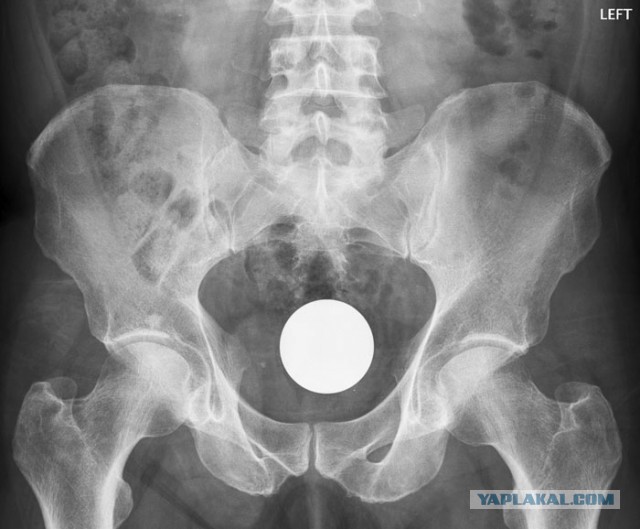

Физику учить надо. Создаешь вакуум, шар сам вылетит

Шар №12